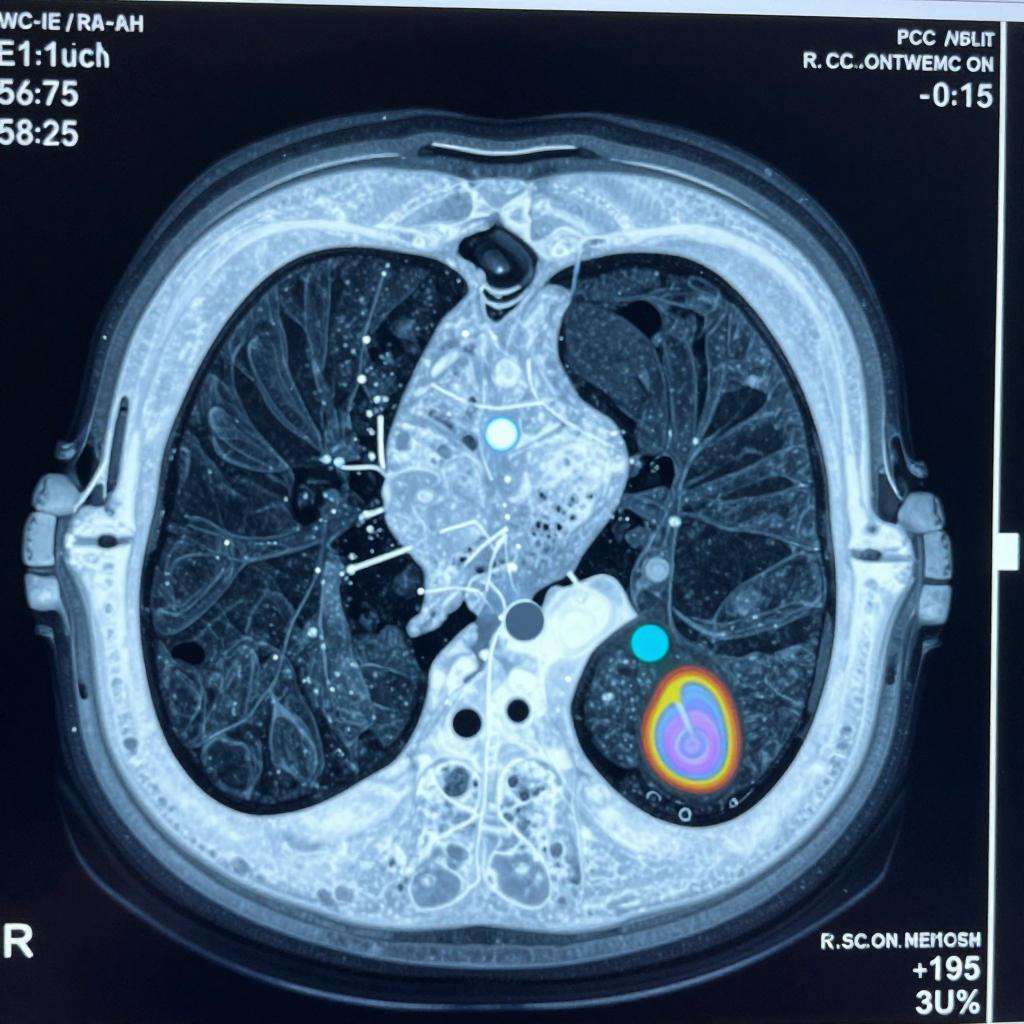

在一场肺癌CT影像人工智能系统演示中,10余张检测图像,通过云端上传系统后十几秒,一个小红圈出现在影像上,圈定范围即为系统自动识别的病灶,准确率达93.9%。除了识别速度高于年轻病理医师外,准确率也很高。而这仅是AI+医疗影像应用场景的冰山一角。

根据汇医慧影测算,仅通过智能初诊系统平台,乳腺疾病影像诊断便可节约60-70%时间,胸片诊断能节约近50%的时间;在准确率上,通过各家医院数据自我迭代以及模型精准调优,目前已达到95%以上。

一方面,病种的医疗价值。企业普遍会选取患者数量大、应用AI影像系统后能获得明显效果和效率提升的病种。比如,大部分AI医疗创业企业刚开始都选择肺结节,因为肺癌在中国发病率、死亡率排名第一,肺结节的筛查有助于预防肺癌,因此这一场景就有很大医疗价值。汇医慧影也是在最初选定肺结节,目前对该病的筛选准确率最高可达95%,3mm的肺结节检出率达85%。